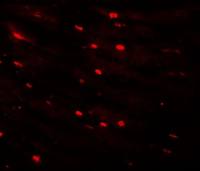

IHC-P analysis of human cortex using GTX89558 Parvalbumin antibody, C-term.

Antigen retrieval : citrate buffer pH 6

Dilution : 2.5μg/ml